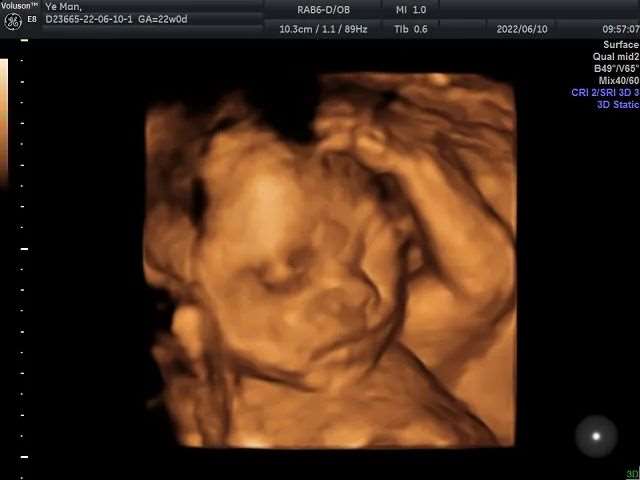

二、四维彩超大排畸检查

检查时间:孕中期22-28周

(无需空腹、无需憋尿)

四维彩超(九大畸形筛查)是产检中不可忽略的检查项目之一,其图像清晰直观,还有立体成像功能,跟普通的B超不同。它可以检查到胎宝宝宫内动态发育情况、肢体运动、胎儿的吞咽动作等,观察胎儿是否有大体畸形,多角度、多方位进行胎儿异常评估,包括检查眼面部、心脏的异常、体表的畸形、消化系统、泌尿系统等异常。

筛查胎儿畸形,为诊断胎儿先天性体表畸形提供更准确的依据,一定程度上提高了诊断质量。

孕中期这项四维检查可以说是重中之重,宝妈们一定要提早预约哦!要不然很可能会约不上哦!